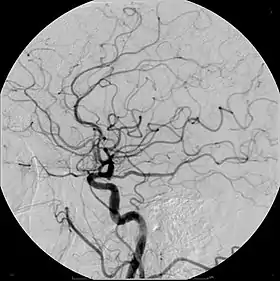

![]() Example of iodine-based contrast in cerebral angiography | |

Digital subtraction angiography (DSA) is a fluoroscopy technique used in interventional radiology to clearly visualize blood vessels in a bony or dense soft tissue environment. Images are produced using contrast medium by subtracting a "pre-contrast image" or mask from subsequent images, once the contrast medium has been introduced into a structure. Hence the term "digital subtraction angiography.[1][2] Subtraction angiography was first described in 1935 and in English sources in 1962 as a manual technique. Digital technology made DSA practical starting in the 1970s.[3][4]